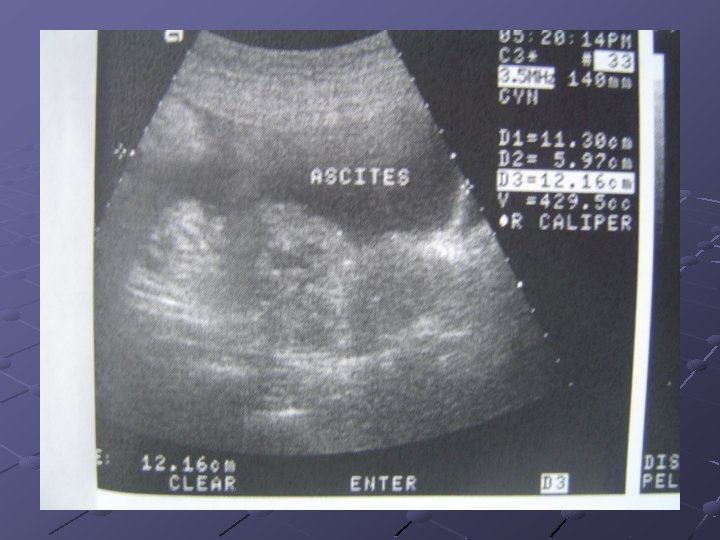

Contoh yang umum adalah kanker kolorektal menyebar ke hati melalui aliran darah. Ovarian Cancer Iii Chief Complaint Fullness Of Abdomen